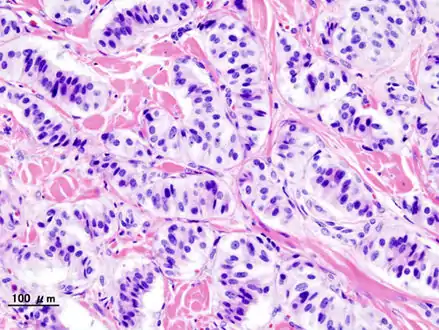

Pathology of pancreatic endocrine tumour (insulinoma). | |

- Pancreatic insulinoma